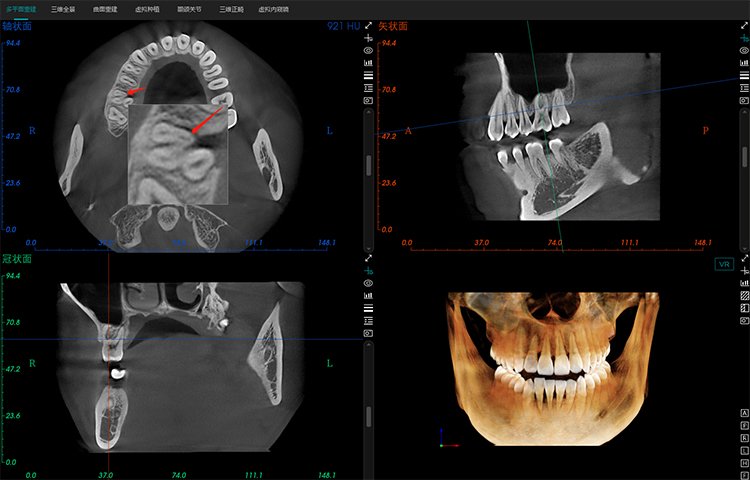

- Amplio campo de visión, satisfaciendo las necesidades clínicas generales.

- Potente funcionalidad, mejorando fácilmente la eficiencia clínica.

Potente Funcionalidad

El software de diagnóstico 3D líder de Meyer y el sistema de análisis ortodóntico inteligente adoptan un diseño de UI modular, lo que hace que las funciones del software sean más cercanas a las necesidades clínicas y más fáciles de usar para los médicos, reduciendo significativamente el costo de aprendizaje.

Software de Diagnóstico 3D

MyDentViewer